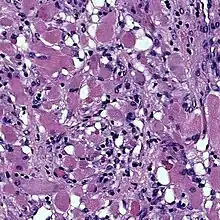

Photomicrograph of fetal-type rhabdomyoma: Note the plump, pink benign skeletal muscle cells.

Cardiac rhabdomyomas are the most common primary tumor of the heart in infants and children. It has an association with tuberous sclerosis.[2] In those with tuberous sclerosis, the tumor may regress and disappear completely, or remain consistent in size. A common histological feature is the presence of Spider Cells, which are cardiac myocytes with enlarged glycogen vacuoles separated by eosinophilic strands, resembling the legs of a spider.